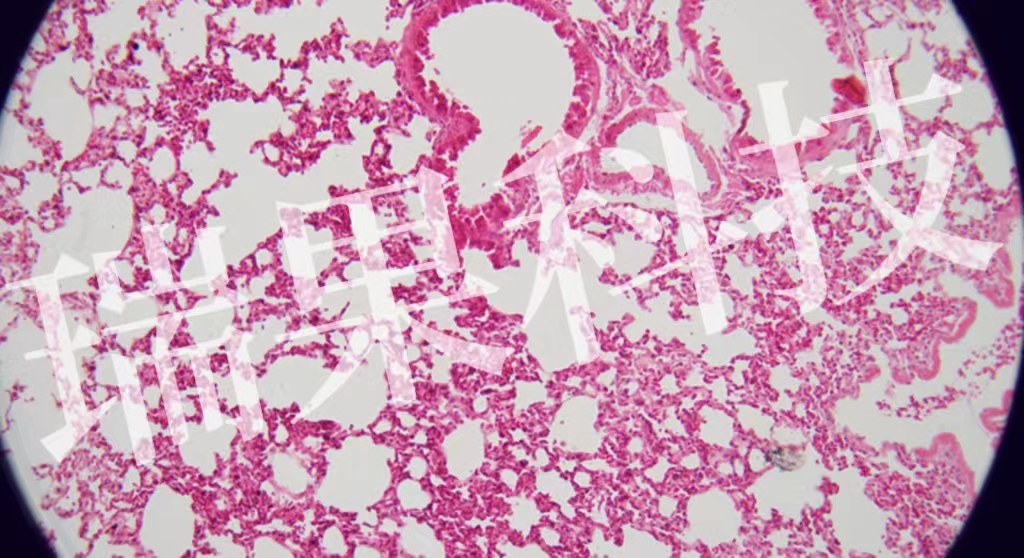

HE染色:蘇木精 - 伊紅染色法 ( hematoxylin-eosin staining ) ,簡稱HE染色法 ,石蠟切片技術(shù)里常用的染色法之一 。蘇木精染液為堿性 ,主要使細胞核內(nèi)的染色質(zhì)與胞質(zhì)內(nèi)的核酸著紫藍色 ;伊紅為酸性染料 ,主要使細

HE染色:蘇木精 - 伊紅染色法 ( hematoxylin-eosin staining ) ,簡稱HE染色法 ,石蠟切片技術(shù)里常用的染色法之一 。蘇木精染液為堿性 ,主要使細胞核內(nèi)的染色質(zhì)與胞質(zhì)內(nèi)的核酸著紫藍色 ;伊紅為酸性染料 ,主要使細胞質(zhì)和細胞外基質(zhì)中的成分著紅色 。HE染色法是組織學(xué)、胚胎學(xué)、病理學(xué)教學(xué)與科研中最基本、使用最廣泛的技術(shù)方法。

肺2-1-20x